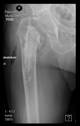

The radiological examination allowed us to verify the close bone-to-implant contact and the unchanged position of the implant during follow-up.

In all the cases operated with the above-described targeting procedure, the stems of the cups remained between the cortical bone surfaces without perforation of the linea terminalis, as shown by postoperative radiographs. There were no complicated surgical situations. In 16 cases, the wound healings were uneventful, and the hips were able to bear weight again after postoperative rehabilitation.